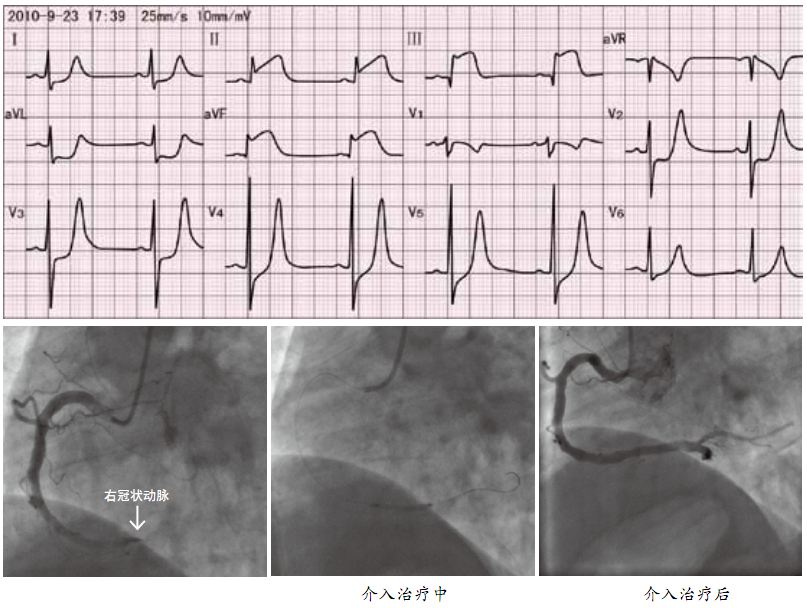

心肌梗死的檢查

以下就是關(guān)于心肌梗死的檢查的具體介紹: